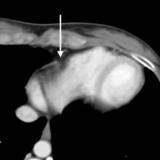

Peric stripe - slightly thickened

close up

Date: 03/17/2004

Views: 3834